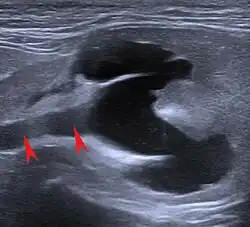

An X-ray examination can be used to detect changes in the size, density and position of the kidneys as well as some urinary stones (struvite and calcium oxalate stones are "radiopaque") and soft tissue calcifications. In severely emaciated cats or fluid accumulations in the retroperitoneal space, however, the kidney can only be visualized to a limited extent on the X-ray image due to the resulting reduction in contrast. Excretory urography, in which a radiopaque contrast medium (e.g. Iopamidol, Iohexol) is injected into the bloodstream and its excretion via the kidneys is recorded radiographically. This makes it possible to detect circulatory disorders, dysfunctions of the renal corpuscles and obstructions of the outflow pathways.[22]

The ultrasound examination allows morphological changes in the kidneys in more detail. In addition to changes in size and shape, renal cysts, localized (focal) organ damage, water sac kidneys and urinary retention as well as tumors can also be visualized. Hardly defined (diffuse) organ changes are accompanied by changes in echogenicity, but can only rarely be assigned to defined diseases.[22] Pulsed Wave Doppler" can also be used to detect circulatory disorders.[23] Calcification (nephrocalcinosis) is also common in chronic kidney disease and can also be detected sonographically.[24]